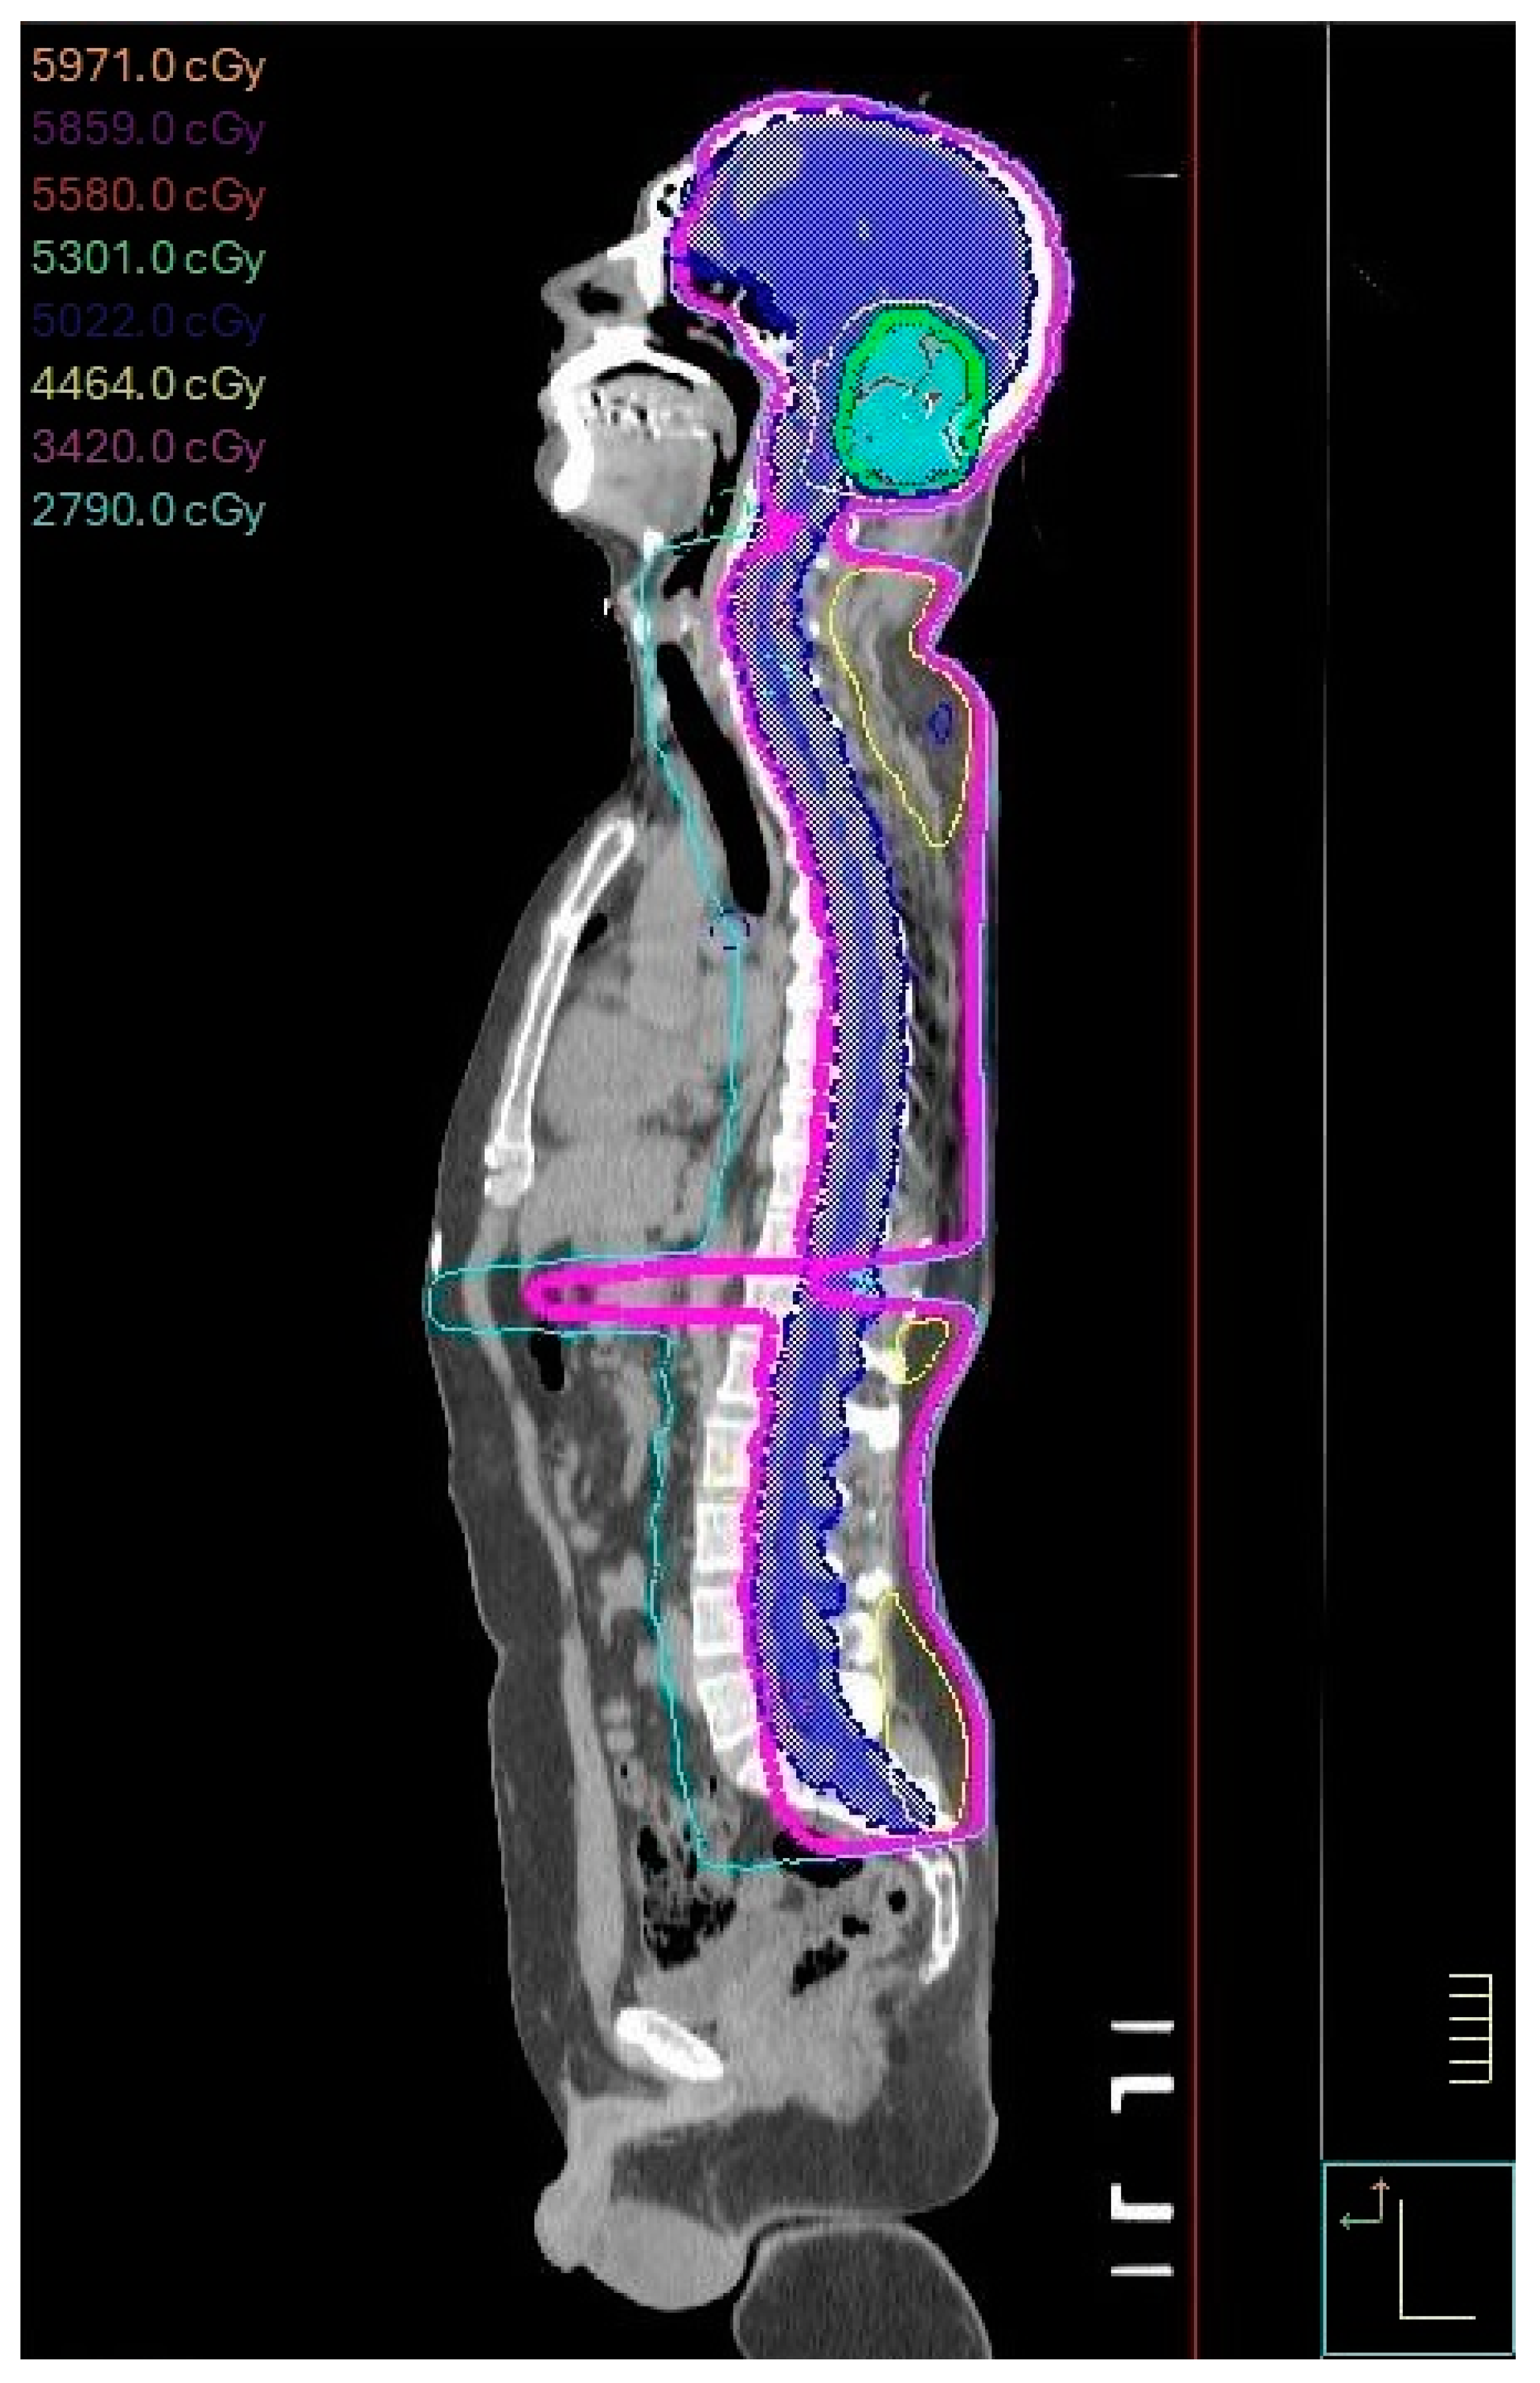

2.2. Treatment